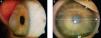

Central toxic keratopathy (CTK) is presented as a central corneal opacity accompanied by stromal tissue loss after LASIK53 (Fig. 2). Its etiology is still unknown, although it has been proposed that uncontrolled enzymatic degradation during wound healing process might be the pathological substrate. CTK is a rare non-inflammatory condition that presents acutely and is painless.53 Anterior segment tomography has shown corneal surface flattening with consequent hyperopic shift.64 It is a self-limited condition that usually resolves within 18 months and most patients recover visual function, even though a faint corneal haze and hyperopic shift may persist in over time.53,64

Central Toxic Keratopathy with loss of central corneal transparency. Image reproduced under Creative Commons Attribution License. Hazin R et al., 2010. Middle East Afr J Ophthalmol. http://www.ncbi.nlm.nih.gov/pmc/articles/PMC2880375/.